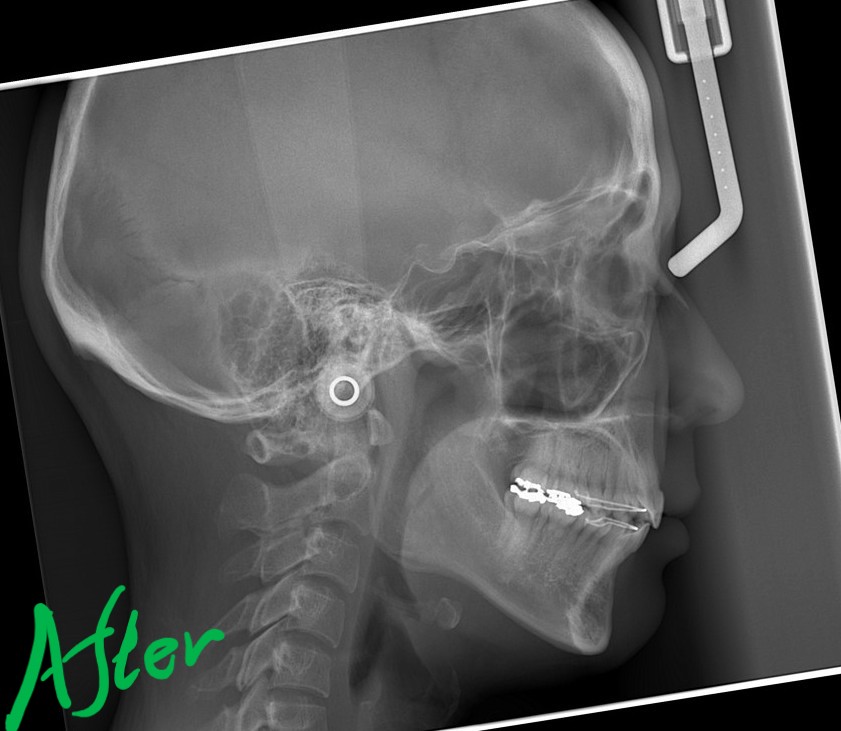

レントゲン写真でも矯正治療前後を比較してみましょう

【After】